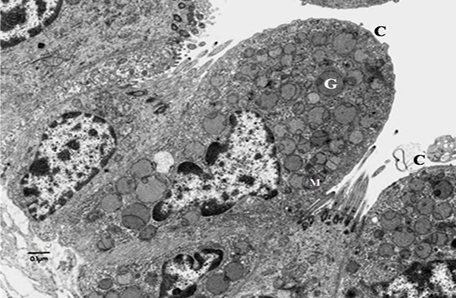

TEM photo of cells lining small bronchiole:

cubical ciliated cells and Clara cell